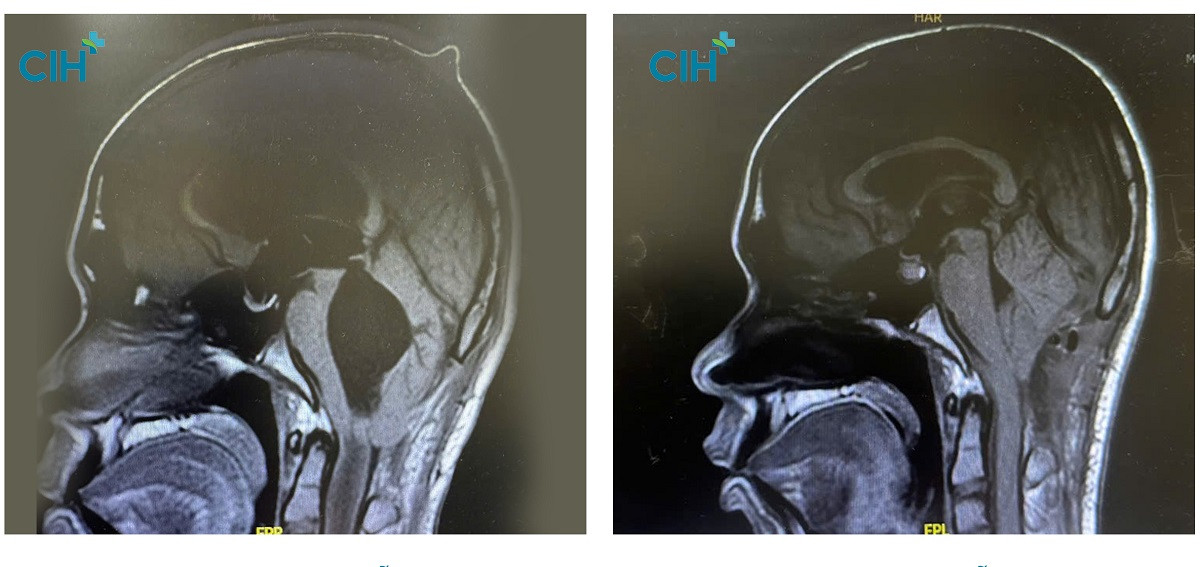

| Hình ảnh chụp MRI vùng đầu của bệnh nhân trước và sau phẫu thuật |

Tuy nhiên, đó chỉ là bước đầu trong hành trình điều trị. Hình ảnh MRI sau đó xác nhận bệnh nhân mắc hội chứng Arnold-Chiari, với hạnh nhân tiểu não tụt xuống đốt sống cổ C1, gây tắc nghẽn dịch não tủy và hình thành ống rỗng tủy kéo dài tới tận đốt sống ngực D9. Các bác sĩ tiếp tục tiến hành phẫu thuật mở rộng lỗ chẩm và cắt cung sau đốt sống C1 nhằm khơi thông dòng chảy dịch não tủy.